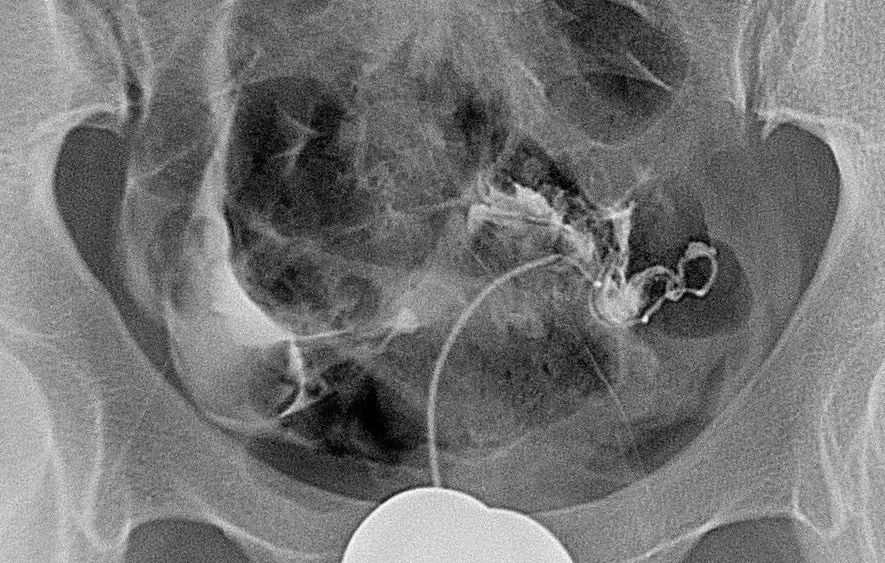

巨块型肝癌,很难通过一次性介入治愈

输卵管性不孕症,很可能一次介入再通即可达成“做妈妈”的目标